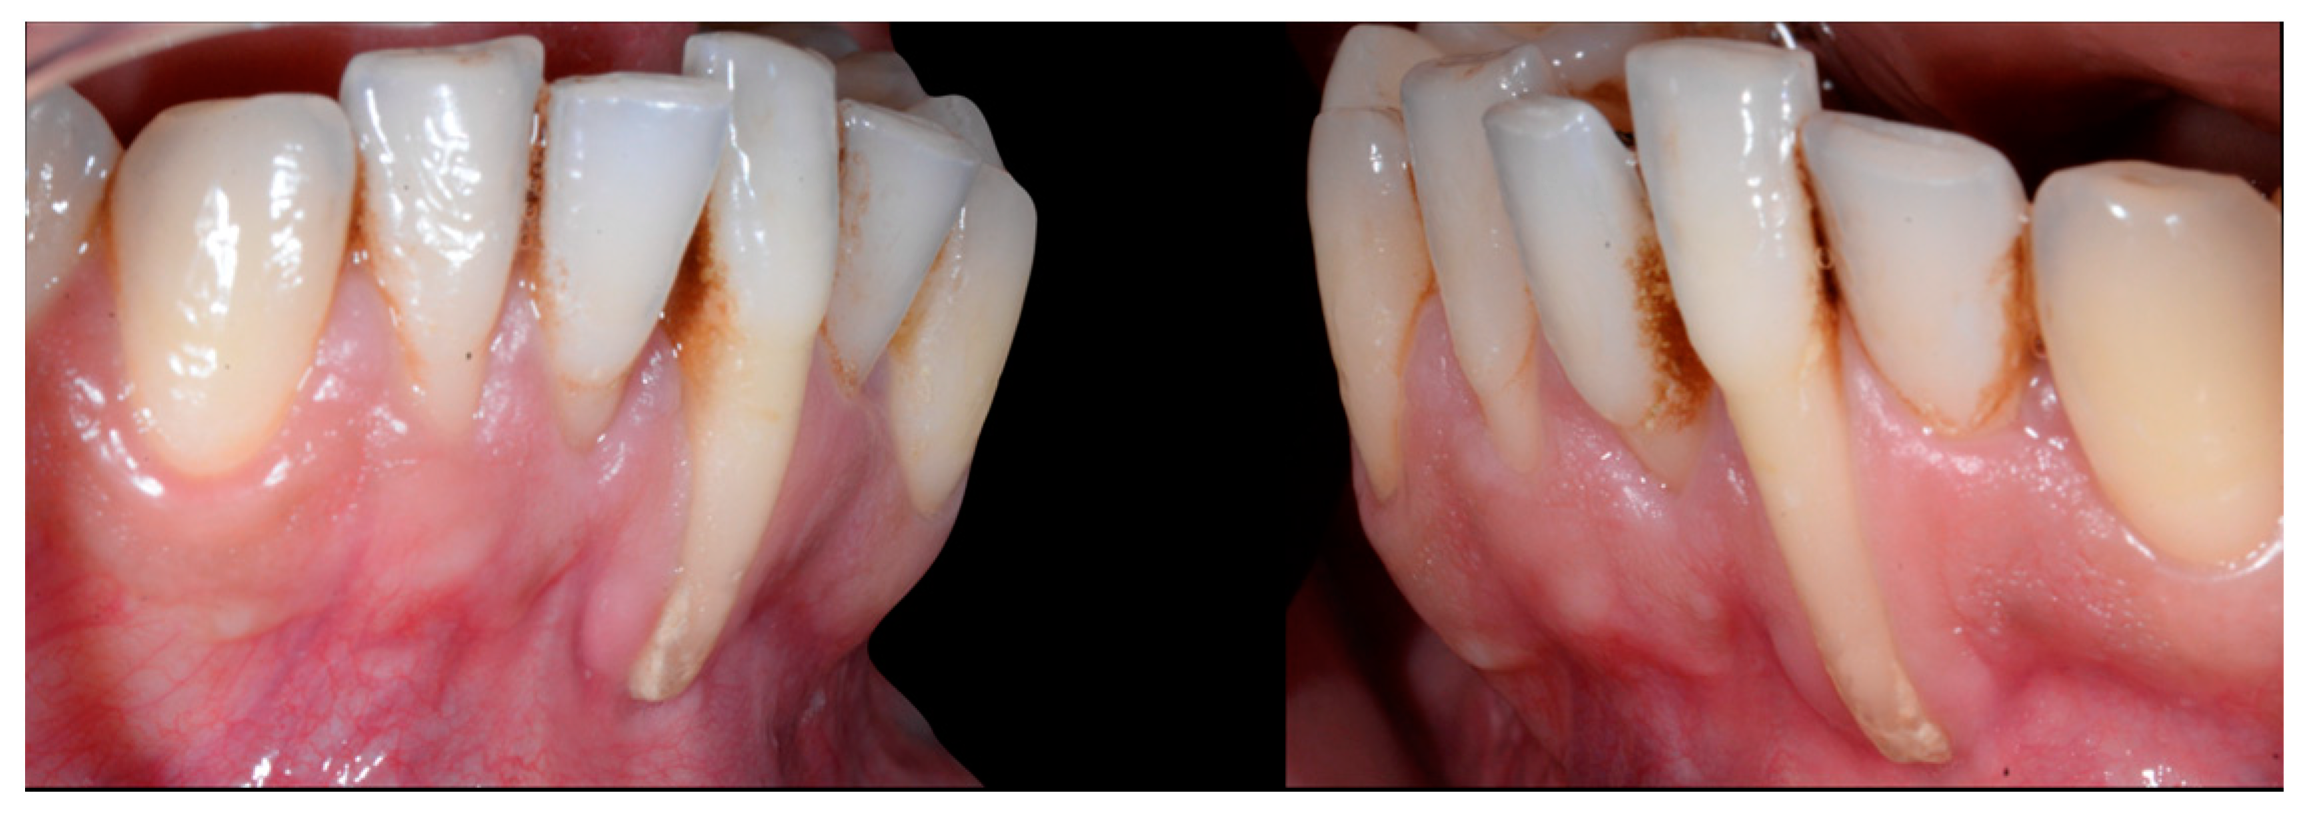

The root of tooth 21 is visible through the gingiva (Figure 7). Figure 8 shows the extent of gingival recession on tooth 41.

Figure 7.

Intermediate wire syndrome. Lateral view.

Figure 8.

Intermediate wire syndrome. Lateral views.

In Figure 6, 11 and 21 show a difference in incisal edge height and gingival margin. Tooth 41 shows gingival recession to the muco-gingival junction (Cairo’s RT1) with root visibility. Tooth 33 had a significant lingual tilt (coronal–lingual torque), not symmetrical to tooth 43.

Figure 6.

Intermediate wire syndrome. Frontal view.